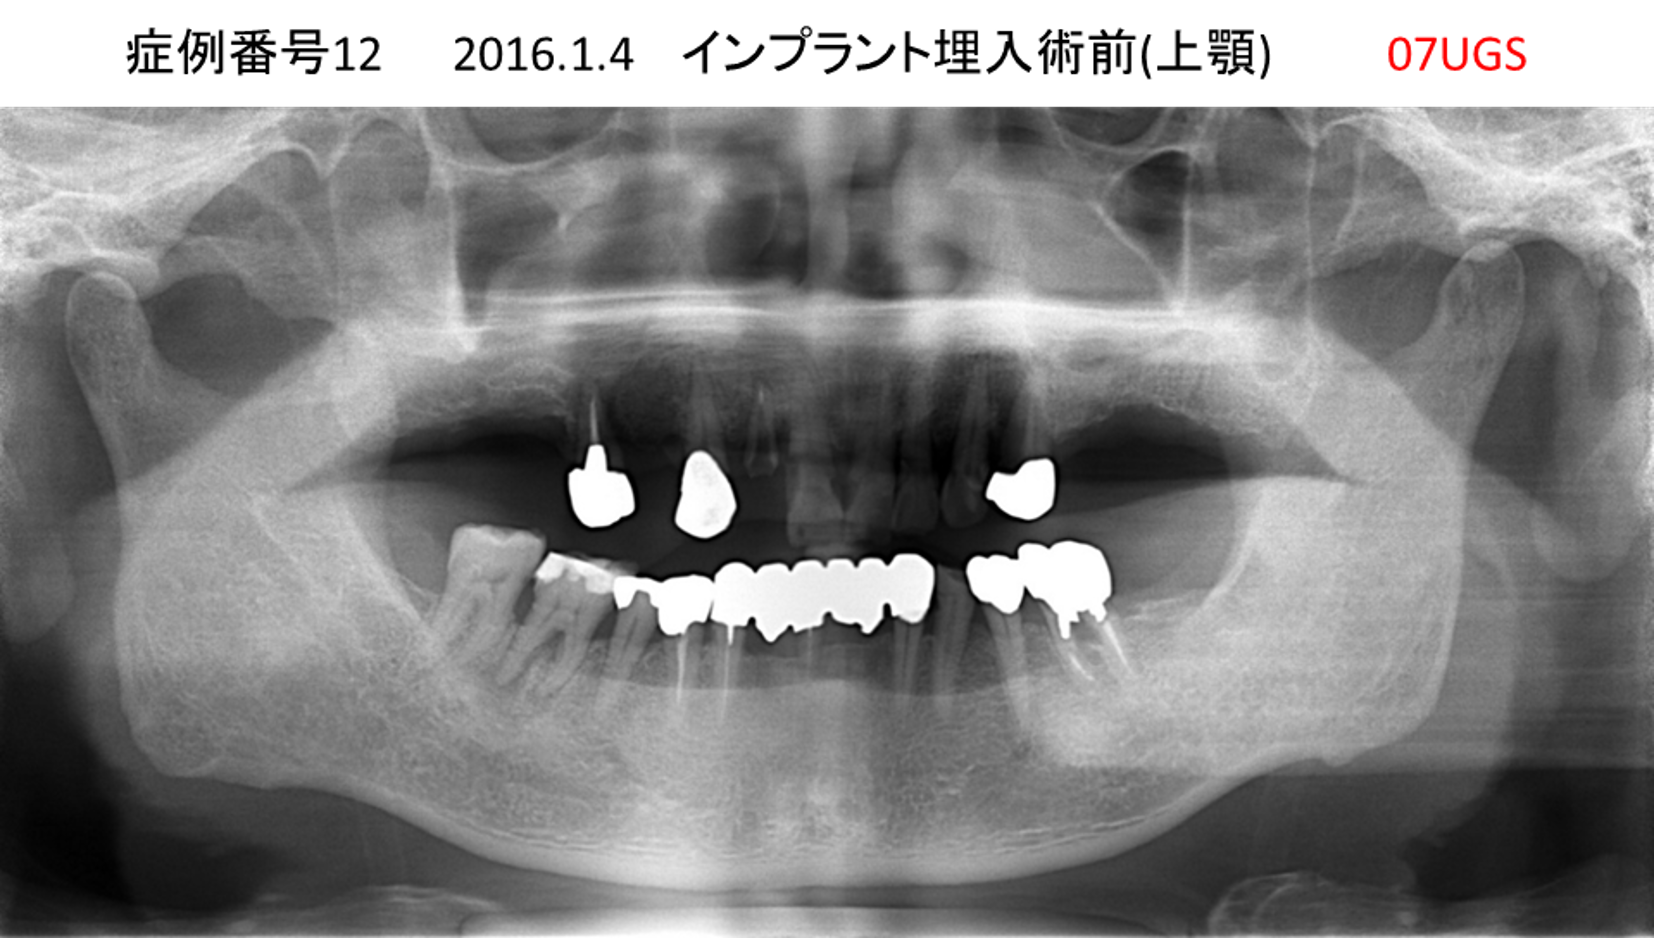

上の前歯が揺れてきてかめない患者様のインプラント症例

| 治療名称 |

インプラント |

| 治療費用 |

440万円+税 |

| 治療期間 |

6か月 |

| 患者さんの症状(主訴) |

上の前歯が揺れてきた。かめない |

| 治療内容 |

サイナスリフト、GBR、インプラント、即時荷重 |

| 治療結果 |

上の前歯の揺れが収まった。奥歯でしっかり噛める。 |

| 治療の注意点(リスク/副作用) |

インプラントが壊れたら再治療が必要 |